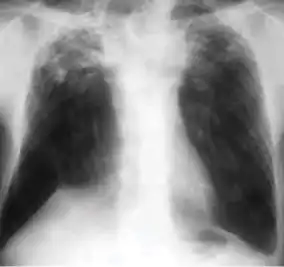

Chest X-ray of a person with advanced tuberculosis: Infection in both lungs is marked by white arrow-heads, and the formation of a cavity is marked by black arrows.